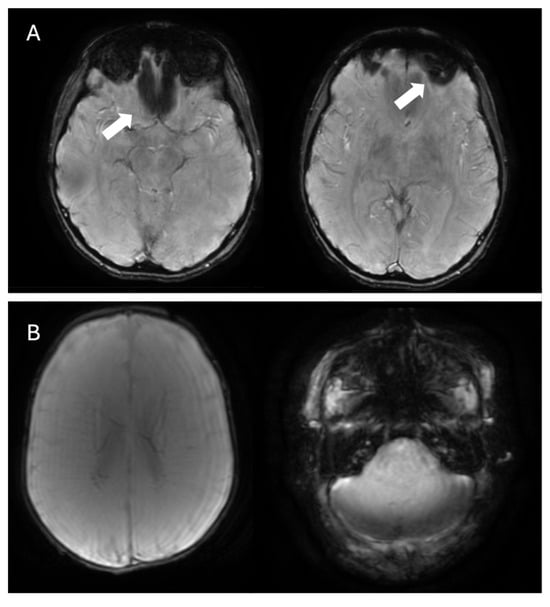

4.1. Parkinson’s Disease, Lewy Body Dementia, and Atypical Parkinsonian Syndromes

- Schwarz, S.T.; Afzal, M.; Morgan, P.S.; Bajaj, N.; Gowland, P.A.; Auer, D.P. The ‘Swallow Tail’ Appearance of the Healthy Nigrosome—A New Accurate Test of Parkinson’s Disease: A Case-Control and Retrospective Cross-Sectional MRI Study at 3T. PLoS ONE 2014, 9, e93814. [Google Scholar] [CrossRef] [PubMed]

- Cheng, Z.; He, N.; Huang, P.; Li, Y.; Tang, R.; Sethi, S.K.; Ghassaban, K.; Yerramsetty, K.K.; Palutla, V.K.; Chen, S.; et al. Imaging the Nigrosome 1 in the substantia nigra using susceptibility weighted imaging and quantitative susceptibility mapping: An application to Parkinson’s disease. NeuroImage Clin. 2020, 25, 102103. [Google Scholar] [CrossRef]

- Schmidt, M.A.; Engelhorn, T.; Marxreiter, F.; Winkler, J.; Lang, S.; Kloska, S.; Goelitz, P.; Doerfler, A. Ultra high-field SWI of the substantia nigra at 7T: Reliability and consistency of the swallow-tail sign. BMC Neurol. 2017, 17, 194. [Google Scholar] [CrossRef] [PubMed]

- Gao, P.; Zhou, P.-Y.; Li, G.; Zhang, G.-B.; Wang, P.-Q.; Liu, J.-Z.; Xu, F.; Yang, F.; Wu, X.-X. Visualization of nigrosomes-1 in 3T MR susceptibility weighted imaging and its absence in diagnosing Parkinson’s disease. Eur. Rev. Med. Pharmacol. Sci. 2015, 19, 4603–4609. [Google Scholar] [PubMed]

- Mahlknecht, P.; Krismer, F.; Poewe, W.; Seppi, K. Meta-analysis of dorsolateral nigral hyperintensity on magnetic resonance imaging as a marker for Parkinson’s disease. Mov. Disord. 2017, 32, 619–623. [Google Scholar] [CrossRef]

- Shams, S.; Fällmar, D.; Schwarz, S.; Wahlund, L.-O.; van Westen, D.; Hansson, O.; Larsson, E.-M.; Haller, S. MRI of the Swallow Tail Sign: A Useful Marker in the Diagnosis of Lewy Body Dementia? Am. J. Neuroradiol. 2017, 38, 1737–1741. [Google Scholar] [CrossRef]

| Parkinson’s disease, Lewy body dementia, and atypical parkinsonian syndromes | Absent swallow-tail sign | Loss of the normal bright signal in the posterior third of the substantia nigra (nigrosome-1) |